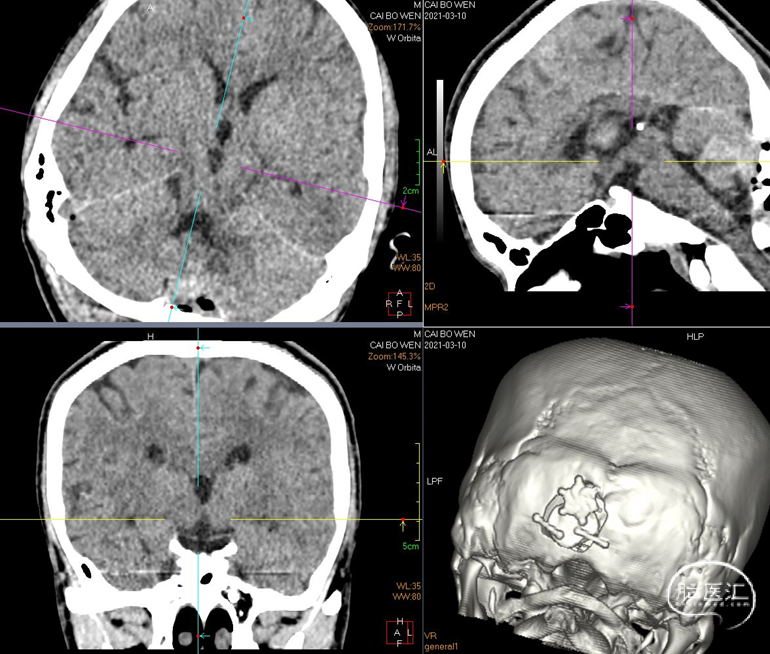

脑干海绵状血管瘤是一种多发的海绵状血管瘤。患者于2017年发现海绵状血管瘤,2018年由于反复出血做手术,手术效果好。2020年11月,患者头痛并有出血症状。2020年12月再次出血,第二次手术。复查CT,情况良好。